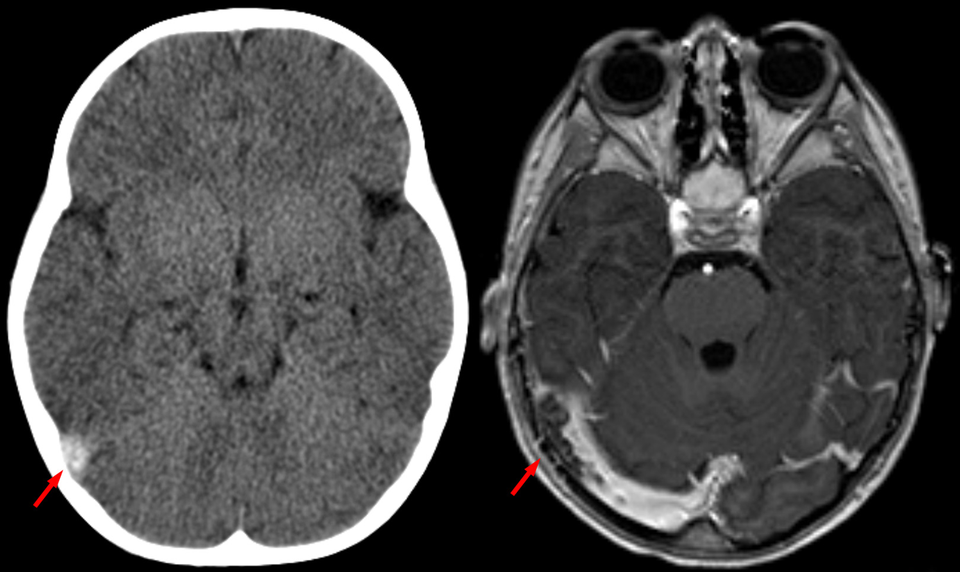

Sinusvenenthrombose. Sinusvenenthrombose. © wikimedia/Hellerhoff (CC BY-SA 3.0)